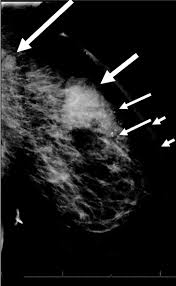

What Does Inflammatory Breast Cancer Look Like On Mri - Breast Cancer Gynecology And Obstetrics Msd Manual Professional Edition / Inflammatory breast cancer pictures show a red and/or swollen breast that appears inflamed.. You may notice dimpling or pitting, and the skin on your breast. Cancer begins when uncontrollably change and grow, forming a sheet of cells called a tumour. It blocks the lymph vessels in the skin of your breast. Inflammatory breast cancer inflammatory breast cancer is a rare type of breast cancer that develops rapidly, making the affected breast red, swollen and tender. Symptoms of inflammatory breast cancer include swelling (edema) and redness (erythema) that affect a third or more of the breast.

When the cancer grows into the rest of the body through the blood vessels and lymph vessels, breast cancer spreads. Inflammatory breast cancer occurs when cancer cells block the lymphatic vessels in skin covering the breast, causing the characteristic red, swollen appearance of the breast. Inflammatory breast cancer inflammatory breast cancer is a rare type of breast cancer that develops rapidly, making the affected breast red, swollen and tender. A breast mri usually is performed after you have a. The usual cause of inflammatory breast symptoms is breast mastitis or duct ectasia.

The features of a malignant breast condition on mri scan are often to do with the outer irregular borders of a lesion. Inflammatory breast cancer affects breast tissue and can appear unusually dimpled or thick. Absence of lump or breast mass in a patient suffering from an inflammatory skin condition of the breast, suggests the presence of skin or subcutaneous inflammatory condition caused by either infection or inflammatory breast cancer. The skin looks like the skin of an orange, and may be discolored with painful and itchy breast. The breast is enlarged (often of relatively short onset), indurated, erythematous, warm, and may be tender and painful. But not every woman who has been diagnosed with breast cancer needs a breast mri. What does breast cancer look like on a mammogram? A lump in the breast. Breast mri is sometimes used in women who already have been diagnosed with breast cancer, to help measure the size of the cancer, look for other tumors in the breast, and to check for tumors in the opposite breast. Most cases are invasive ductal carcinomas, which develop in the cells lining the milk ducts and spread throughout the breast. The breast can also be painful in inflammatory breast cancer, but this is not always the case. Evaluating the impact of preoperative breast magnetic resonance imaging on the surgical management of newly diagnosed breast cancers. When the cancer grows into the rest of the body through the blood vessels and lymph vessels, breast cancer spreads.

Inflammatory breast cancer is an an aggressive and fast growing breast cancer in which cancer cells infiltrate the skin and lymph vessels of the breast. They're often easy to move around (mobile) and may be tender. Ibc symptoms are caused by cancer cells blocking lymph vessels in the skin causing the breast to look inflamed. symptoms include breast swelling, purple or red color of the skin, and dimpling or thickening of the skin of the breast so that it may look and feel like an orange peel. Unlike traditional forms of breast cancer, inflammatory breast cancers do not develop unusual lumps within the affected breast. The skin is thickened and edematous, classically with a peau d'orange appearance. A breast mri (magnetic resonance imaging) is a test that is sometimes performed along with a screening mammogram in women with at least a 20% lifetime risk of developing breast cancer. What does breast cancer look like on a mammogram? Mri of breast can help breast cancer diagnosis. Inflammatory breast cancer inflammatory breast cancer is a rare type of breast cancer that develops rapidly, making the affected breast red, swollen and tender. A rash isn't the only visual symptom of inflammatory breast cancer. Inflammatory breast cancer (ibc) is rare, making up about 2 to 4 percent of breast cancer cases. Inflammatory breast cancer pictures and symptoms The skin looks like the skin of an orange, and may be discolored with painful and itchy breast.

The Radiology Assistant Mri Of The Breast from radiologyassistant.nl Inflammatory breast cancer pictures and symptoms The breast can also be painful in inflammatory breast cancer, but this is not always the case. The skin of the breast may also appear pink, reddish purple, or bruised. Ridges or thickening of the skin of the breast. Inflammatory breast cancer (ibc) is rare, making up about 2 to 4 percent of breast cancer cases. Need to have physical exam, mammogram, and ultrasound as needed. Sometimes it can be difficult to tell the difference between mastitis and inflammatory breast cancer. Absence of lump or breast mass in a patient suffering from an inflammatory skin condition of the breast, suggests the presence of skin or subcutaneous inflammatory condition caused by either infection or inflammatory breast cancer.